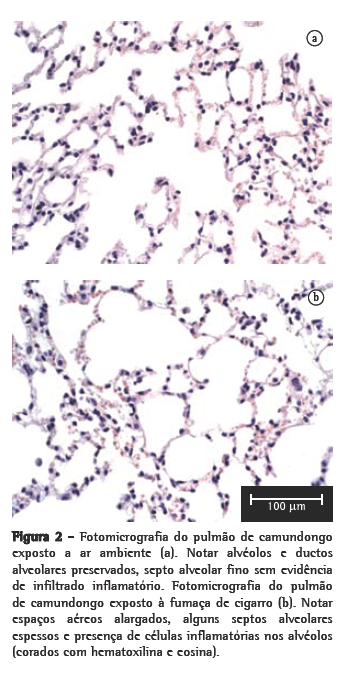

Foi observado um aumento significativo no número de macrófagos alveolares no grupo CS10 (p < 0,001), que foi contínuo de acordo com o tempo de exposição nos grupos CS20, CS30 e CS60 (p < 0,001) em relação ao grupo controle (Figura 1). Entretanto, não foi observado alterações no número de neutrófilos. Na análise histológica, o grupo controle exposto ao ar ambiente apresentou alvéolos preservados com o septo alveolar fino e ocasionais macrófagos alveolares (Figura 2a). Os grupos CS10 e CS20 apresentaram um padrão histológico com alterações progressivas de quebra do septo alveolar com um maior número de macrófagos alveolares. O grupo CS30 apresentou um padrão inicial de alterações da histoarquitetura pulmonar principalmente com alargamentos dos espaços aéreos correspondentes ao ducto alveolar e alvéolos. O grupo CS60 apresentou um padrão típico de enfisema em camundongos com áreas de alargamento de alvéolos e áreas de fibrose inicial (Figura 2b).